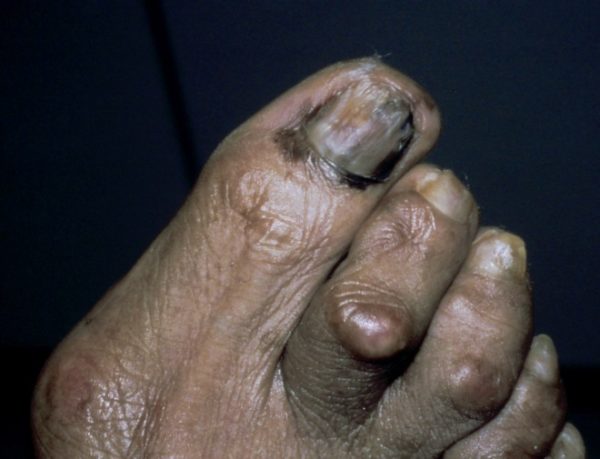

Als unter seinem Zehennagel ein dunkler Fleck erschien, führte Marley dies auf eine Fußballverletzung zurück. Schließlich wurde bei ihm eine seltene, aggressive Art von Hautkrebs diagnostiziert akralentiginöses Melanom (ALM). ALM kommt von „akral“, einem anatomischen Begriff für die peripheren Körperteile, und „lentiginös“ für sommersprossiges Aussehen.

Beispiel für ein akralentiginöses Melanom (kein Foto von Bob Marley). Bildnachweis: Hugh Gloster, MD

Fotos des akralentiginösen Melanoms (ALM).